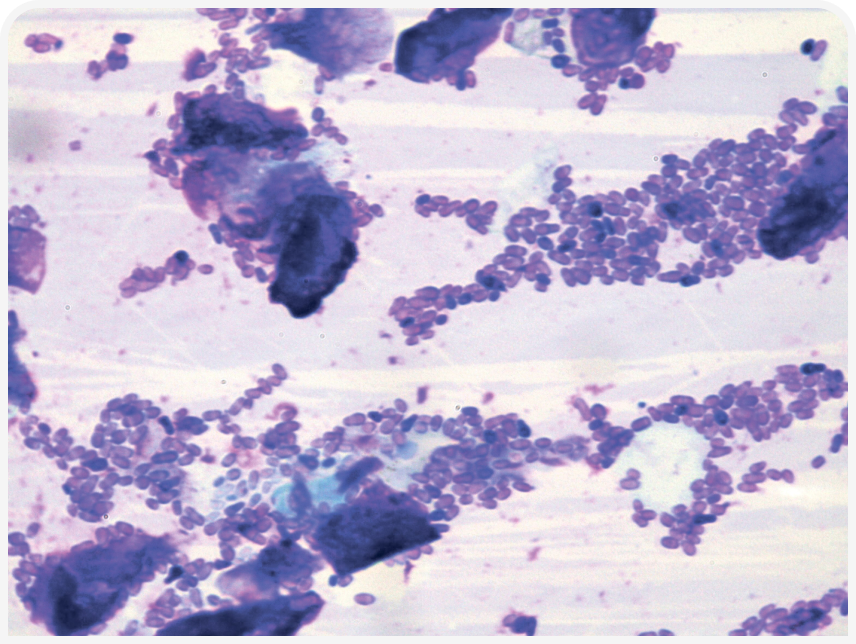

Однако не все случаи отита обязательно приводят к дисбиозу, а в некоторых ситуациях за отит можно принять обильное выделение ушной серы и зуд. Кроме того, цитологические исследования показывают, что нарушение защитных свойств и регуляции микробиома уха приводит к размножению вторичных возбудителей (Рисунки 2 и 3) (5, 6); во всех случаях отита для установления точного диагноза необходимо провести цитологическое исследование, и некоторые советы приведены в Таблице 1.